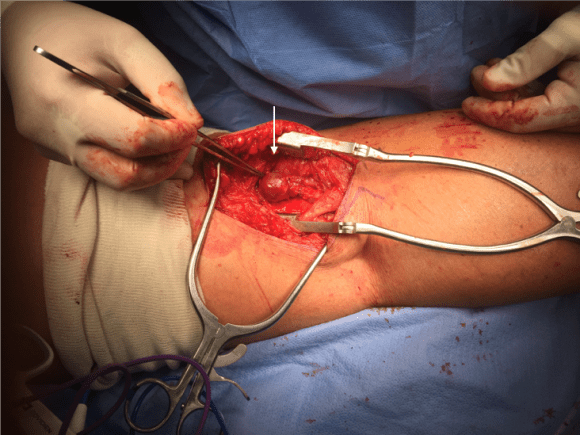

And you can see how well it matches up to the actual operation shown below:

Intraop Photo.png

This was treated with plication of the saccular aneurysm and unlike the fusiform aneurysm, I did not sew over a mandrill (a large 24F foley) inserted through a transverse venotomy, but rather ran a Blalock type stitch under and over a clamp.